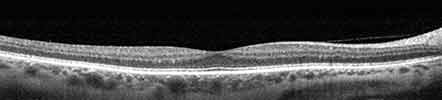

Eye Wellness Exam Examples

Healthy Retina Unhealthy Retina

The OCT Exam is a quick, non-invasive scan that allows our doctors to see all 10 layers of your retina. The Clarus retinal camera gives a view into the periphery of your eye normally not accessible without a dilated pupil.